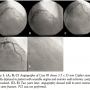

Case #1. A 61-year-old woman presented with angina. Angiography revealed MB of the mid-LAD (Figures 1A and 1B, Video 1). PCI was performed after medical therapy was ineffective. A 2.75 x 23 mm sirolimus-eluting Cypher stent (Cordis Corporation, Miami, Florida) was deployed without complications with complete relief of symptoms (Figure 1C, Video 2). Repeat coronary angiography was performed 4 months later for recurrence of angina and demonstrated in-stent restenosis (ISR) (Video 3) at the site of a partial stent fracture (Figures 1D and 1E, Video 4), which was treated with an everolimus-eluting 2.75 x 12 mm Xience stent (Abbott Vascular, Abbott Park, Illinois) with resolution of symptoms.